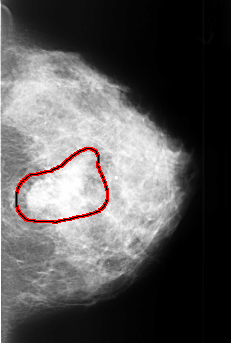

B_3409_1.LEFT_MLO

LEFT_MLO LINES 4408 PIXELS_PER_LINE 2960 BITS_PER_PIXEL 12 RESOLUTION 50 OVERLAY

FILE: B_3409_1.LEFT_MLO.OVERLAY

TOTAL_ABNORMALITIES 1

ABNORMALITY 1

LESION_TYPE MASS SHAPE LOBULATED-IRREGULAR MARGINS OBSCURED-ILL_DEFINED

ASSESSMENT 4

SUBTLETY 4

PATHOLOGY MALIGNANT

TOTAL_OUTLINES 1

BOUNDARY